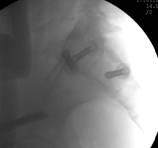

术中C臂

术前CT和术后CT比较

整个手术1小时内完成,通过术后CT影像证实3D打印导航模板引导骶髂螺钉置入安全、准确、创伤较小,手术时间短,患者也很快得到了较好的恢复。